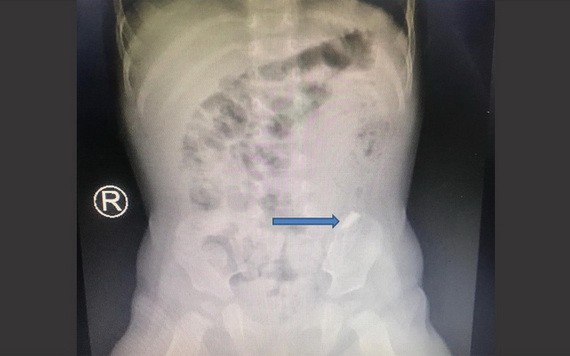

X光照片顯示,病童的大腸處呈現一片碎鏡的異物。(圖源:院方提供)

經X光照片診斷結果顯示,鏡子碎片尺寸與小Kh的身型和腸道相比較大,而且正快速地通過食管、腸胃、幽門、落到十二指腸等。因此,醫生認為施手術十分危險,可能會導致消化道出血、胃腸與食管穿孔等,因鏡子碎片本身是件十分尖銳的物件。後來,由於小Kh減少嘔吐和哭鬧,醫生作出大膽決定:繼續觀察一段時間,每隔4至6小時照一次X光,用胃藥、軟化糞便藥物等,以讓小Kh能夠在大便時可以自動把異物排放出來。所幸兩天後,0.3x1釐米的鏡子碎片已通過小Kh糞便排出來◆